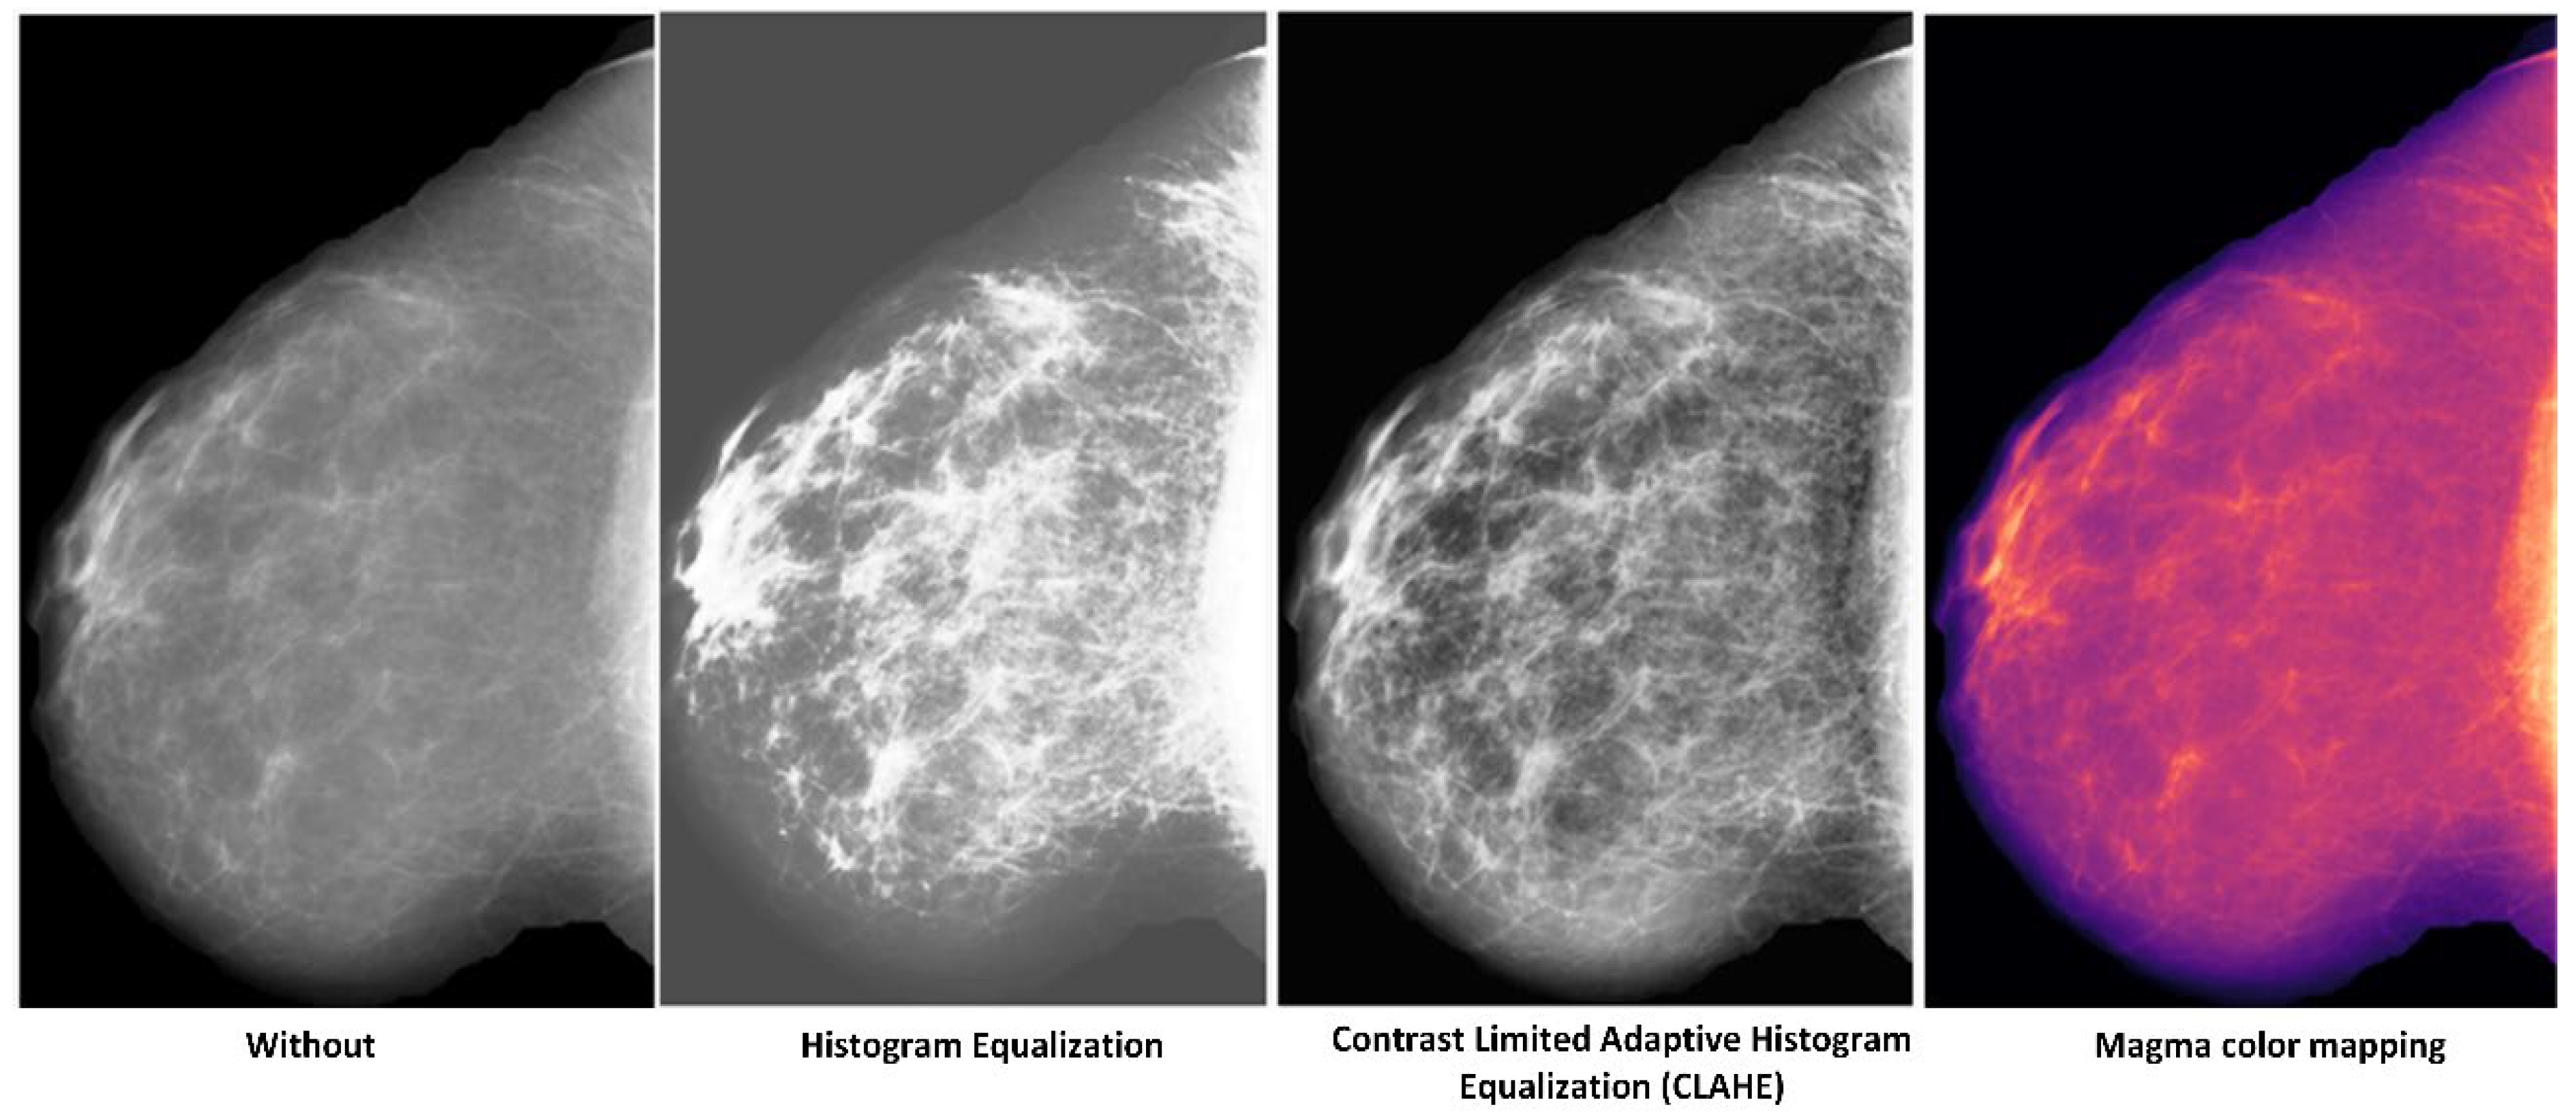

5.1.2. Which Preprocessing Operation?

Breast tissue characteristics in digital mammographic images will be more apparent after image enhancement, increasing the early breast cancer classification rate. A custom-tailored image processing technique will likely be needed to best display different image characteristics. Additionally, different breast density may benefit from specific algorithms and the performance disparities between the image preprocessing methods. As a result, we decided on magma color mapping, as presented in Table 4. An overview of different image preprocessing tasks is shown in Figure 5.

Figure 5.

A comparison of the visual effects of different image preprocessing tasks.